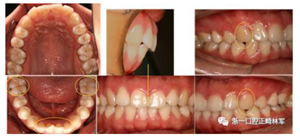

口內(nèi)檢查

恒牙列。上下頜中線對齊。上下頜牙列輕度擁擠。前牙覆合、覆蓋正常。尖牙、磨牙中性關(guān)系。上下前牙基本直立,前牙區(qū)牙根、牙槽骨較突。雙側(cè)上頜尖牙磨耗。

功能及顳下頜關(guān)節(jié)檢查:無關(guān)節(jié)壓痛及彈響,開口度、開口型正常。